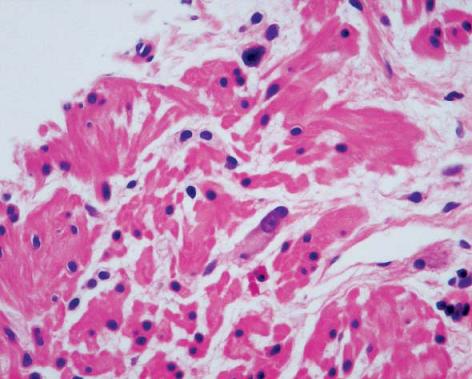

Sometimes what we see is a very immature innervation pattern of ganglion cells similar to that seen in premature infants. These patterns are aggregated into rosette structures with minimal neuropils. Their morphology is different from that of mature neuron cells: they are smaller and bluish-gray, have darker nuclei, are eccentric, their nucleoli are not that prominent, and their cytoplasm is less elongated (11, 12). It is important to learn to recognize these cells and interpret them correctly in order to avoid misdiagnoses of aganglionosis (Figure 9).

Figure 9. Immature ganglion cells arranged in rosette structures. Note that they have small eccentric nuclei and elongated gray-blue cytoplasm (H&E 200X).